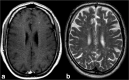

Purpose: Miliary enhancement refers to the presence of multiple small, monomorphic, enhancing foci on T1-weighted post-contrast MRI images. In the absence of a clear clinical presentation, a broad differential diagnosis may result in invasive procedures and possibly brain biopsy for diagnostic purposes.

Methods: An extensive review of the literature is provided for diseases that may present with miliary enhancement on T1-weighted brain MR images. Additional disease-specific findings, both clinical and radiological, are summarized and categorized by the presence or absence of perivascular space involvement.

Results: Miliary pattern of enhancement may be due to a variety of underlying causes, including inflammatory, infectious, nutritional or neoplastic processes. The recognition of disease spread along the perivascular spaces in addition to the detection or exclusion of disease-specific features on MRI images, such as leptomeningeal enhancement, presence of haemorrhagic lesions, spinal cord involvement and specific localisation or systemic involvement, allows to narrow the potential differential diagnoses.